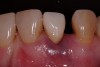

A 54-year-old, non-smoking woman presented with a root fracture at the maxillary right lateral incisor (Figure 1). The patient presented with a 10-mm pocket at the mid-facial probing depth, and a Grade 2 mobility. The preoperative peri-apical digital radiograph can be seen in Figure 2. A natural diastema existed on the distal aspect of the right maxillary incisor, and the patient did not wish to have this corrected. To hold the natural tissue emergence profiles throughout the treatment phase, the immediate implant placement and provisionalization procedure was chosen to treat the affected site. Before the procedure, an occlusal index and registration was taken so that when the retrofitting of the natural tooth shell was accomplished, the exact location of the natural tooth shell could be seated on the implant abutment at the time of implant placement (Figure 3). After administration of an appropriate local anesthetic, tooth No. 7 was removed by an atraumatic technique to preserve the natural soft tissue emergence profiles present pre-surgically (Figure 4). After tooth removal, debridement of the extraction socket was accomplished by curettage of the socket, followed by rotary instrumentation with a course #8 round diamond to ensure removal of all remnants of the periodontal ligament, granulation tissue, and localized debris. To aid in the debridement, the patient was started on a preoperative administration of Augmentin 875 mg, taken the day before treatment, and once again 1 hour before the surgical visit. The patient then continued this antibiotic course for a total of 10 days.

Figure 1  Pretreatment clinical view.

Figure 1